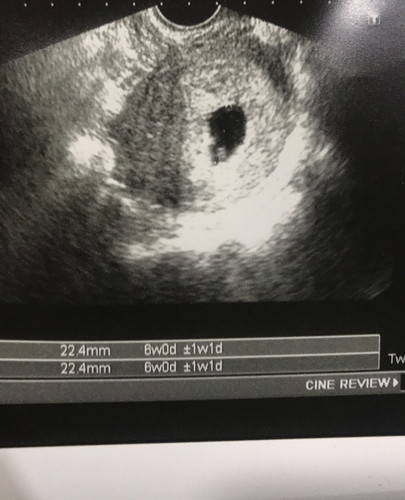

ท้องตามการนับประจำเดือน ได้ 8 วีค มีเลือดออกนิดหน่อยเลยรีบไปหาหมอ บอกอาจจะเป็นแท้งคุกคาม หมอบอกให้คอยเฝ้าระวังอาการถ้ามีปวดถี่ๆนานๆให้รีบมาหาหมอ แต่หมอบอกว่ายังไม่เห็นตัวเด็กเลย ถ้าดูขนาดถุงตั้งครรภ์หมอบอกว่า ท้องแค่ 6วีคเองค่ะ ให้รออีก 2วีคค่อยไปหาหมอใหม่ แต่แม่ๆ เห็นจุดขาวๆนั้นมั้ยคะ คือน้องรึเปล่า แอบมีความหวังค่ะ ว่าจะไม่ท้องลม คุณแม่คนไหนเคยเจอแบบนี้บ้างคะ